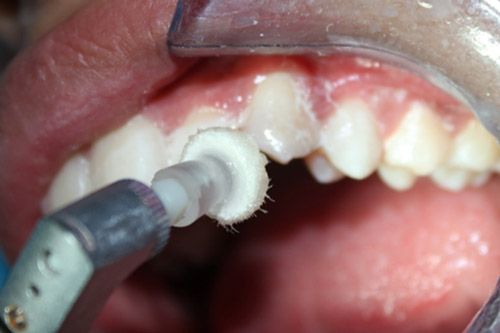

Se decidió utilizar un aeropulidor con bicarbonato Detarfar de Eufar por 1 minuto, con la finalidad de remover el tejido afectado.